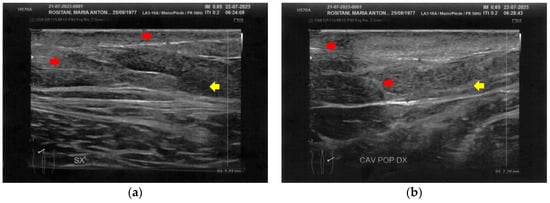

3.1. Basal Imaging Evaluations

3.2. Imaging Evaluations After the Treatment